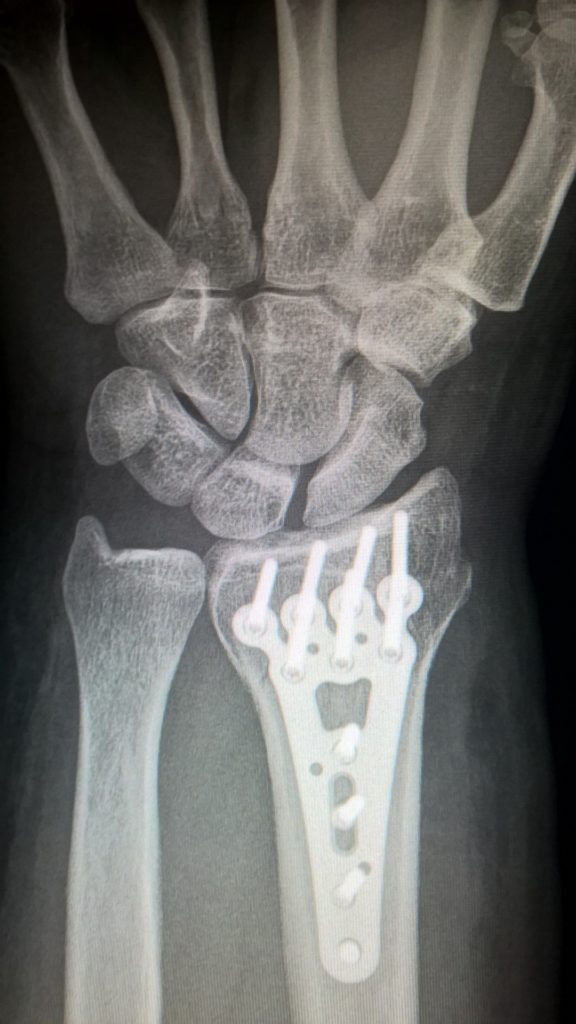

Doktor jabatan mempunyai pengalaman yang luas dalam operasi berteknologi tinggi pada bahagian bawah dan atas menggunakan osteosintesis intramedullary dan tulang yang tersumbat.

Plat biodegradasi yang digunakan dalam operasi untuk menetapkan tulang ulnar, jejari, pergelangan kaki tidak memerlukan penyingkiran berikutnya, iaitu, ia menghilangkan keperluan untuk operasi kedua.